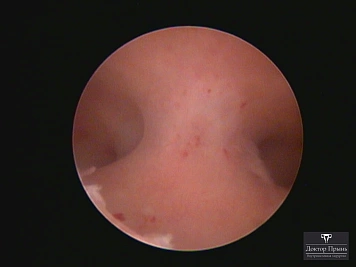

Как правило, синехии находят при УЗИ. Когда по УЗИ патологии нет, а симптомы есть, выполняют гистероскопию – это золотой стандарт в определении синехий.

Гистероскопия позволяет не только увидеть спайки, но и сразу вылечить, т.е. рассечь их. Большинству пациенток подойдёт офисная гистероскопия без наркоза и госпитализации. Среднее время операции 15 минут. Иногда требуется 2-4 операции, чтобы восстановить полость матки.

Синехии, рассечённые Прынь Д.В.